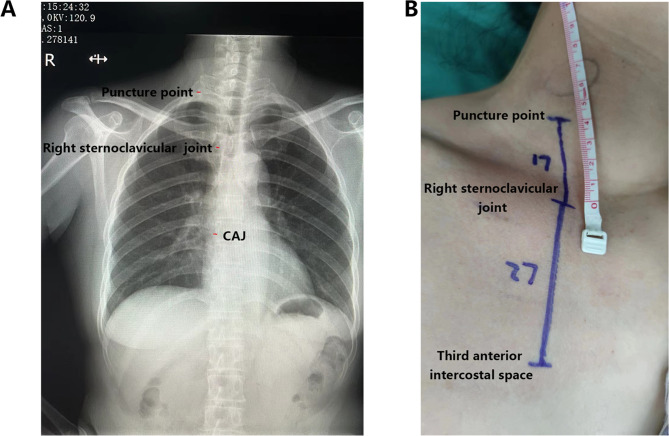

Methods: Clinical information of 117 breast cancer (BRCA) patients who underwent TIVAP implantation was collected. The length of the implanted catheter was determined by a chest radiograph method in the test group, as follows: total catheter insertion length was L, and the distance from the pre-puncture point to the right sternoclavicular joint was measured as L1; the distance from the right sternoclavicular joint to 1.5 vertebral bodies under the trachea carina in the chest radiograph was measured as L2; the preset catheter length was L = L1 + L2. The length of the implanted catheter was determined by a surface measurement method in the control group, as follows: total length of catheter insertion was L; the distance from the pre-puncture point to the right sternoclavicular joint was measured as L1; the distance from the third anterior intercostal space of the right sternoclavicular joint was measured on the body surface as L2; the preset catheter length was L = L1 + L2. CAJ positioning rate and complication rate were compared between the two method groups. Logistic regression analysis, receiver operating characteristic, and decision curve analysis were performed to evaluate the predictive value of the chest radiograph.